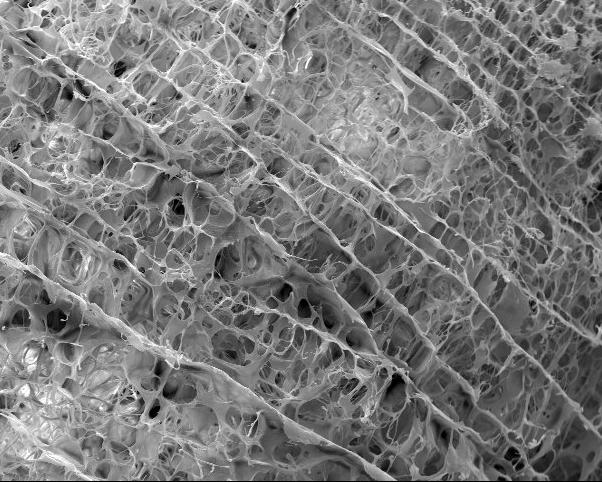

image: A porous scaffold, seen at 250 times magnification, helped heal a torn meniscus. The scaffolded repair was stronger after four weeks than a meniscus that went through the natural healing process.

In lab tests, repairs aided by the scaffold resulted in a stronger meniscus repair after four weeks compared to a meniscus that went through the natural healing process.

The pig-derived scaffold is advantageous over other models including synthetics, because it is processed without chemicals or enzymes, which helps it retain more natural properties, McNulty said. Also, the structure is more porous than other models and even regular meniscus tissue, which allows new cells to move into it more easily to integrate with damaged tissue.